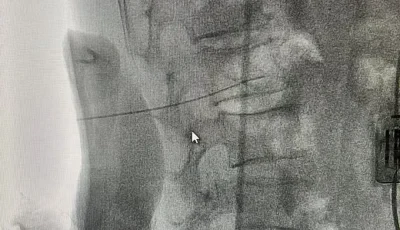

本轮质控聚焦医疗服务核心环节,精准划定质控范围与标准,病历质控重点核查书写规范性、诊疗记录完整性及核心制度落实情况;药事管理紧盯药品储备、处方审核、合理用药等关键流程;超声、影像质控围绕设备操作规范、诊断报告准确性展开评估;护理质控则侧重基础护理落实、院感防控措施执行等细节。质控组通过查阅资料、现场实操考核、医患沟通回访等方式,全面排查医疗服务隐患,对发现的问题现场反馈,逐一制定针对性整改方案,明确整改时限与责任主体。